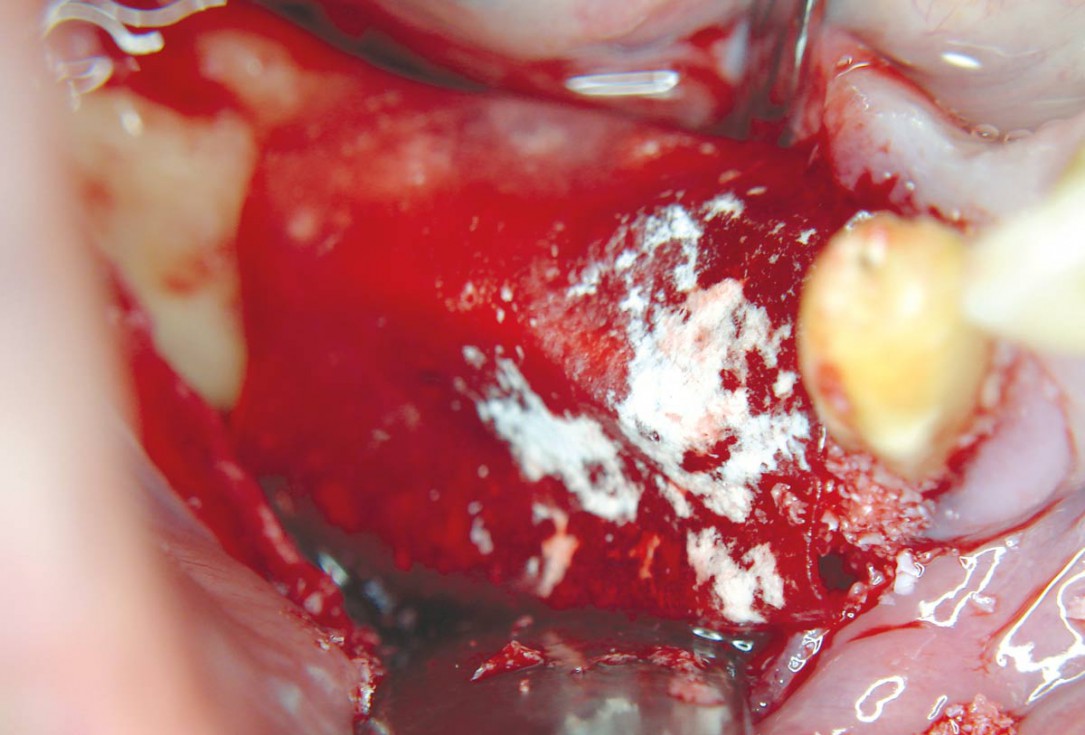

04 / 20 - Decortication of the host bone and fixation of a defect-adapted cortical plateHorizontal ridge augmentation with maxgraft® cortico - M.Sc. E. Kapogianni

05 / 20 - Defect-filling and contouring with cancellous allogenic bone chipsHorizontal ridge augmentation with maxgraft® cortico - M.Sc. E. Kapogianni